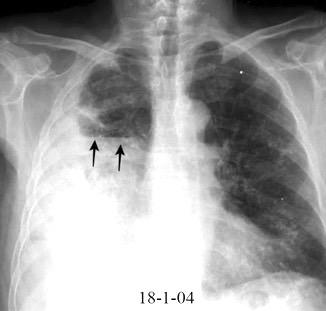

Neumonía a neumococos base izda. con derrame que aumenta.

Broncograma en lateral y en US.

(36-66% en ingresados)